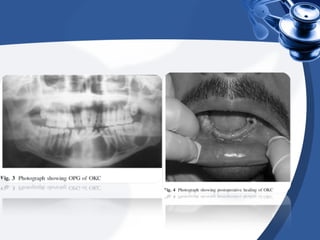

En total fueron 49 pacientes

diagnosticados con queratoquieste

odontogénico, siendo 33 pacientes

masculinos y 16 femeninos. Los

pacientes fueron examinados a

fondo con énfasis en el sitio y el

tamaño de la lesión en la medida

de afectación ósea con radiografías

panorámicas y tomografías

computarizadas